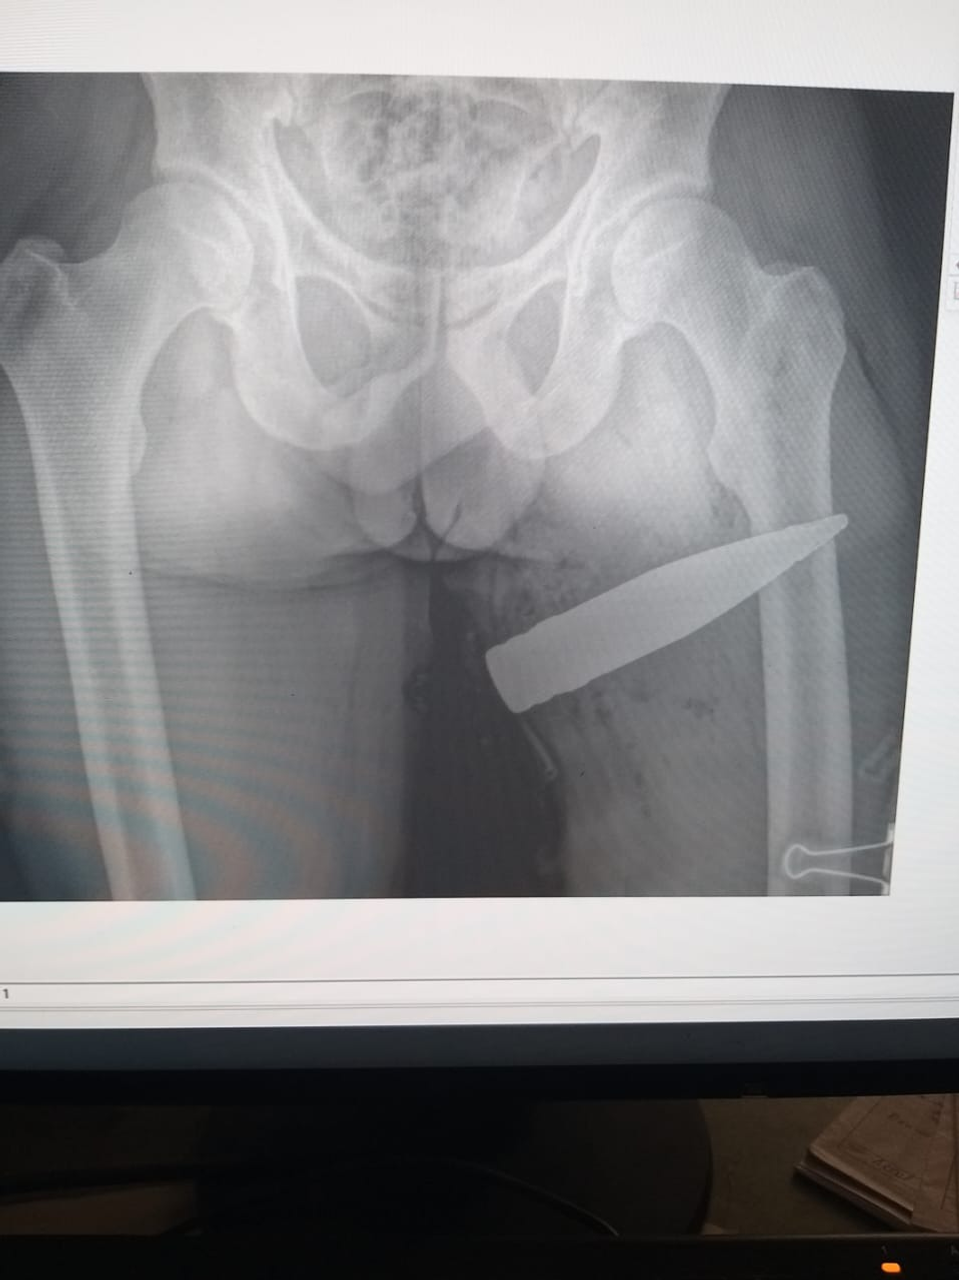

Именно Салават Ахметнурович был тем врачом, который принимал бойца со снарядом. Тот сообщил доктору, что в его бедре застрял осколок. Но когда провели рентген-обследование, стало понятно, что ситуация гораздо серьезнее.

«Сразу сообщил командованию и дежурному военному хирургу. Весь персонал эвакуировали, выставили оцепление и началась операция под наблюдением саперов. Нам с Азатом Рустэмовичем оперировать не разрешили, потому что гражданские врачи. Мы находились на подстраховке», – вспоминает Салават Исламов.